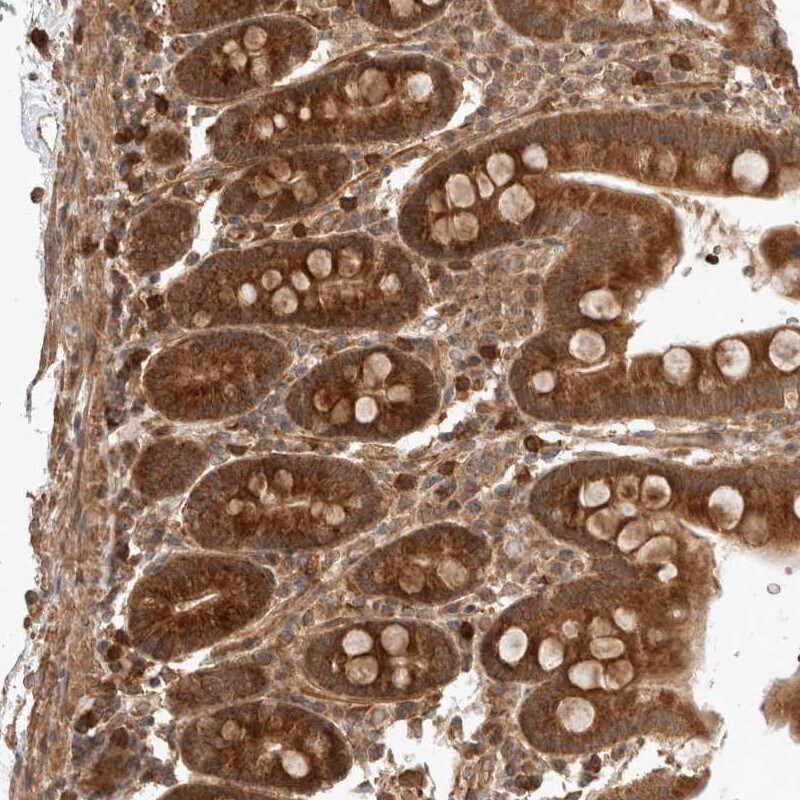

Supportive validation

- Submitted by

- Invitrogen Antibodies (provider)

- Main image

- Experimental details

- Immunohistochemical analysis of ZNF649 in human duodenum using ZNF649 Polyclonal Antibody (Product # PA5-55340) shows strong cytoplasmic positivity in glandular cells.